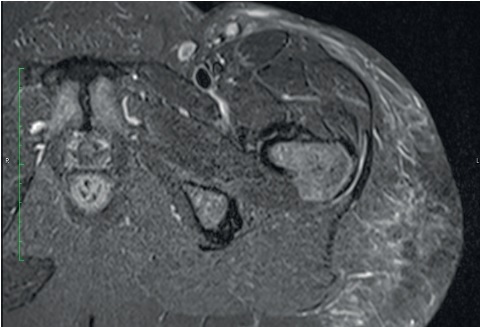

Em março de 2006, a paciente voltou à consulta, relatando o surgimento de nódulo endurecido e doloroso, de 7cm, na face lateral da coxa esquerda há um ano. Após avaliação ultrassonográfica, que descreveu formações ecogênicas de limites imprecisos no subcutâneo da face e xterna da coxa esquerda, região inguinal esquerda e face interna da coxa direita, foi colhida biópsia incisional de lesão, cujo estudo anatomopatológico revelou tumor lipomatoso atípico, com pesquisa negativa para germes comuns, fungos e micobactérias. Em fevereiro de 2012, a exérese dessa lesão (Figura 2) revelou extensa esteatonecrose ao exame histopatológico. A ressonância magnética realizada após a cirurgia evidenciou, além de múltiplos linfonodos de aspecto inespecífico nas cadeias ilíacas e femorais, infiltração líquida no subcutâneo da região glútea (Figura 3).